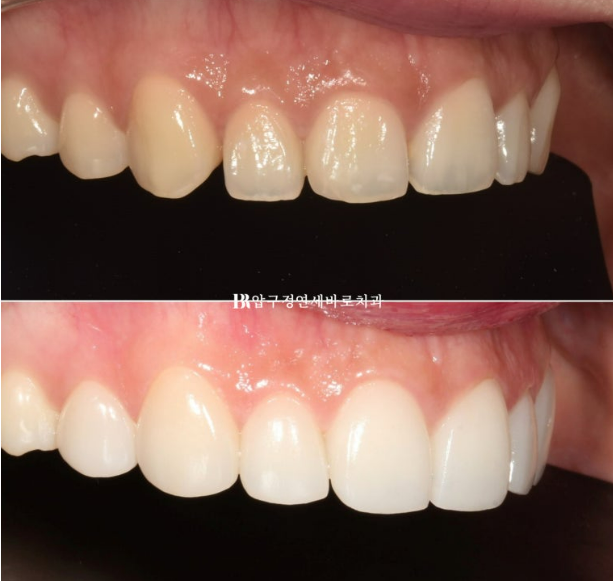

The spaces between the teeth were filled with laminates.

The canines were made to preserve the existing tooth length as much as possible, and from the lateral incisors toward the front teeth, the vertical length was gradually increased,

recreating a smile line with a gentle curved arc downward.

If you look at the front before-and-after photos, the change in the smile line is even clearer.

Shall we draw the smile line?

A natural smile line changes the impression.

A smile line parallel to the lower lip